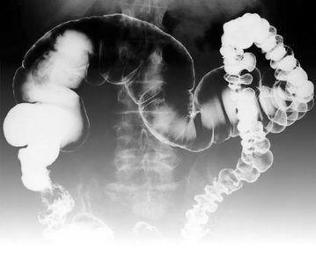

老年人炎症性肠病(senile inflammatory bowel disease,IBD)一般指炎症性肠病患者发病时的年龄大于60或65岁,此外,还指一部分老年人炎症性肠病患者是在年轻时发病,病程延续到60或65岁以上。由于老年人所处的特殊年龄阶段,肠病的病因,鉴别诊断以及处理比年轻人会更复杂,如缺血性肠病,感染性肠病以及药物相关性肠炎等。[1]